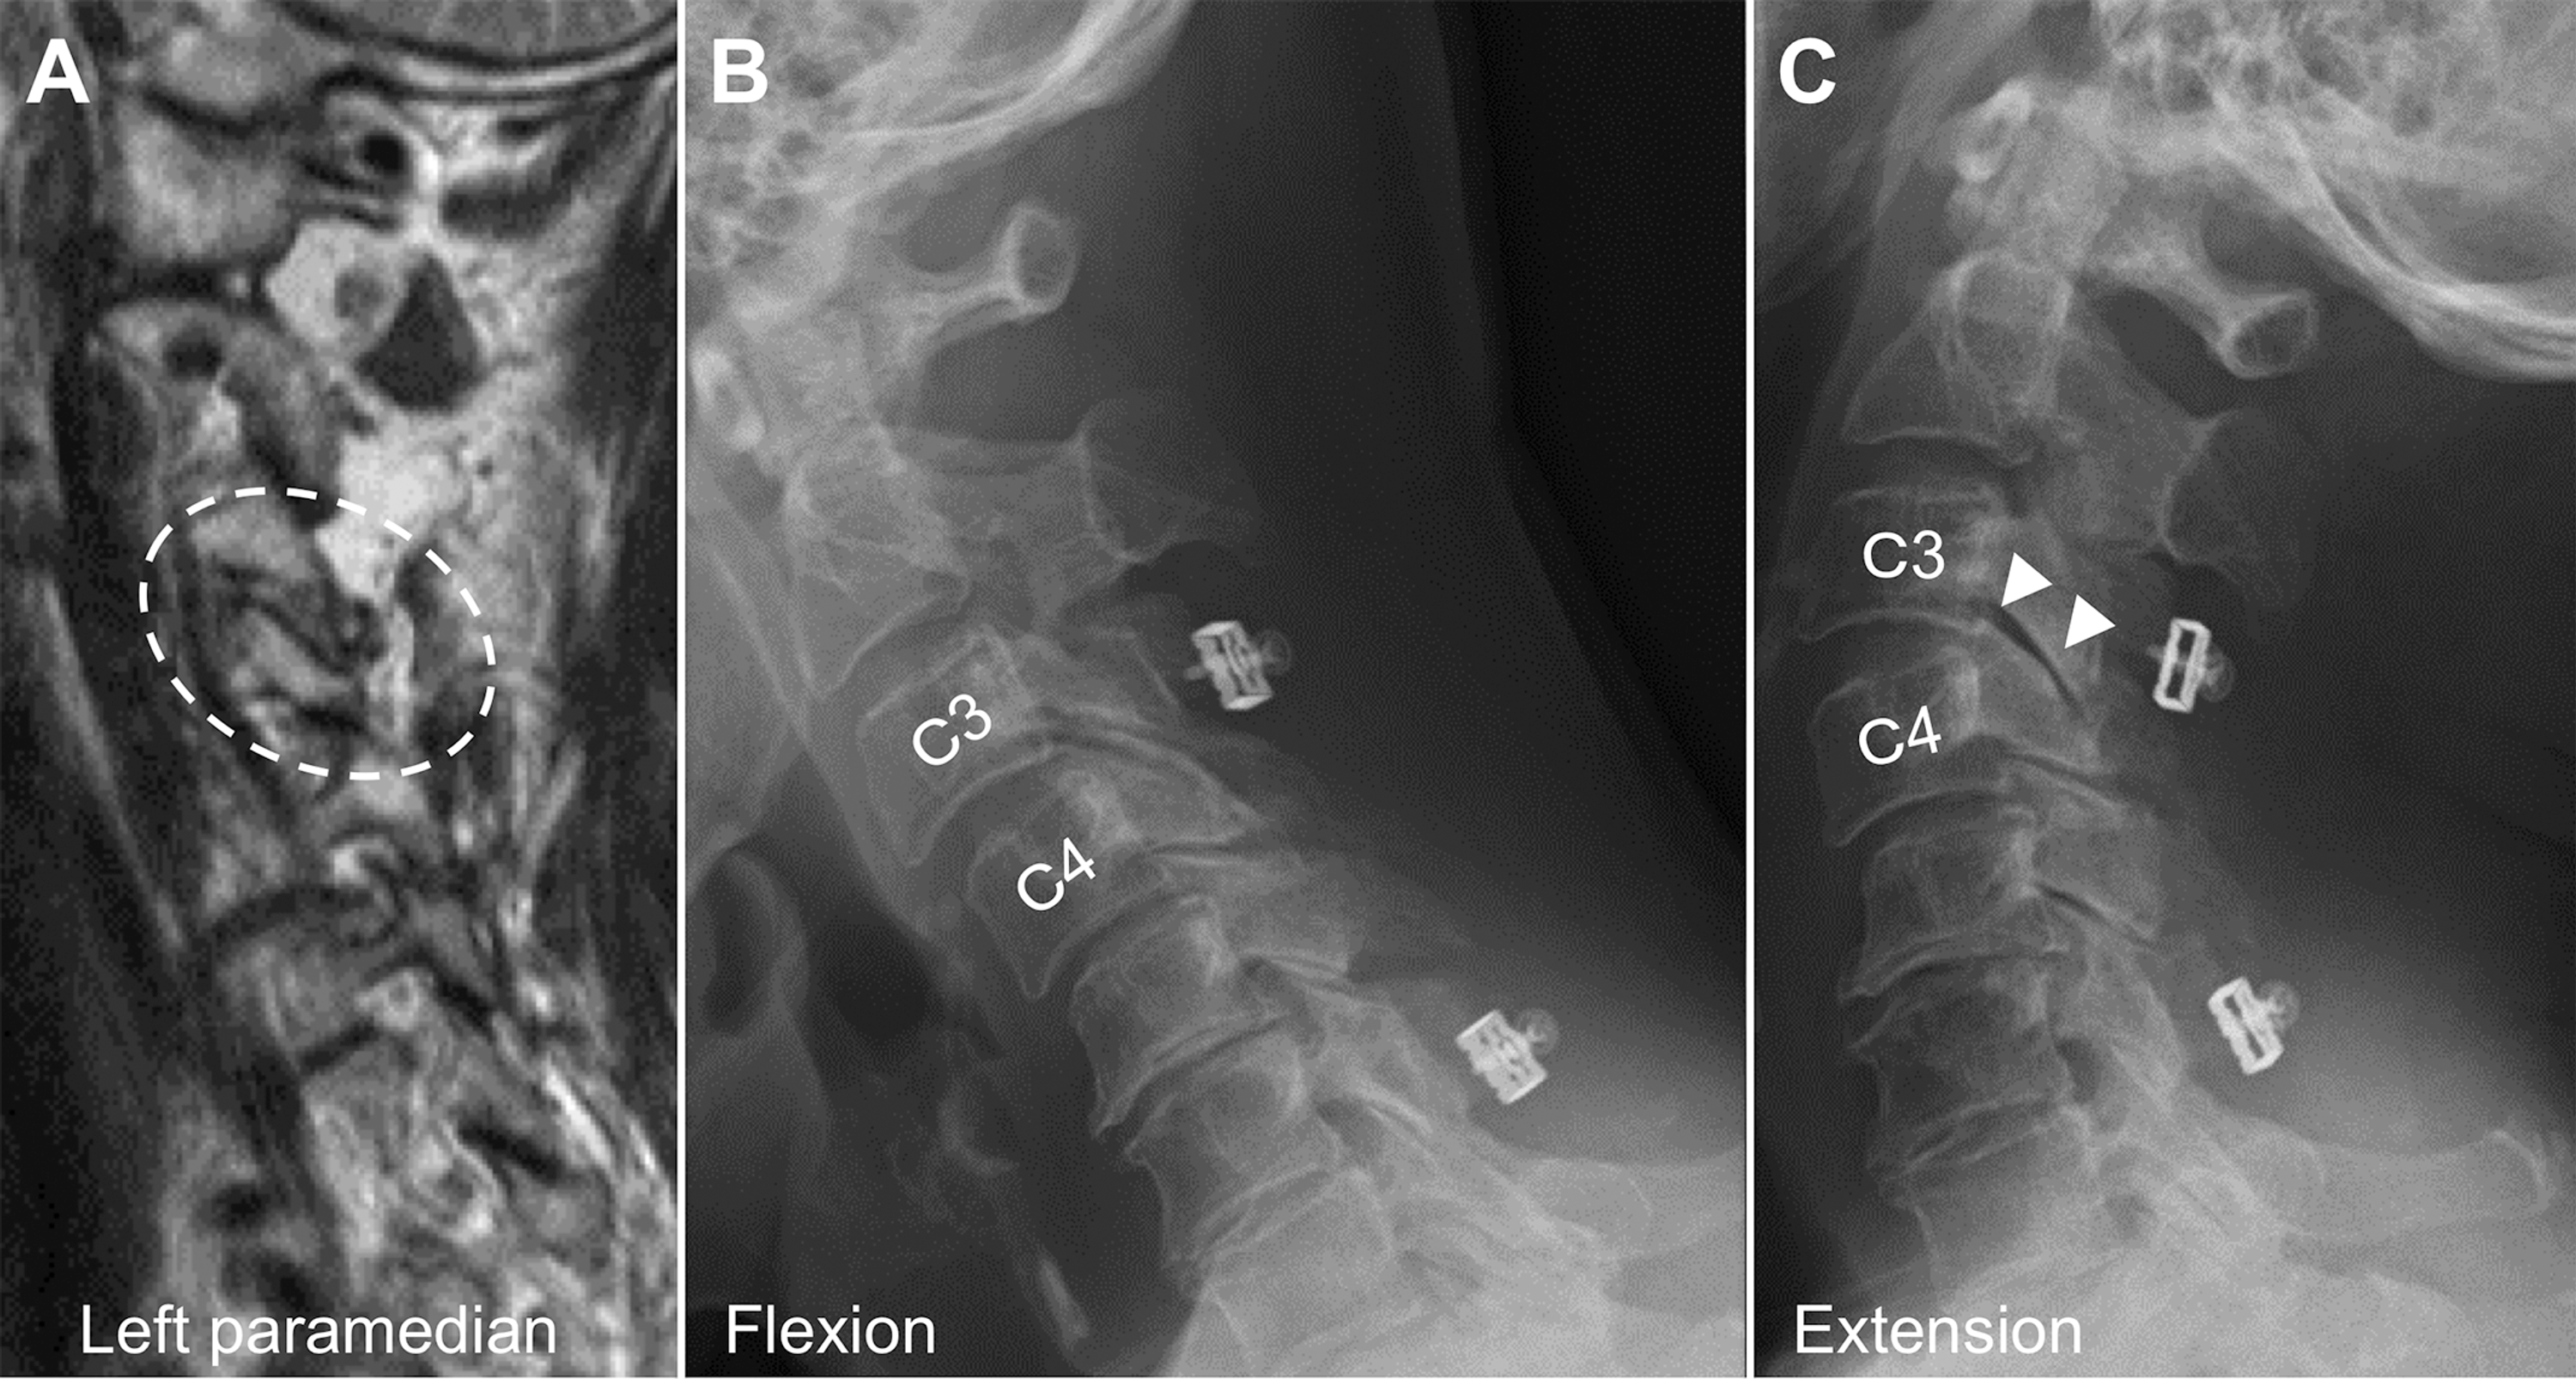

From pubs.rsna.org

Differential Diagnosis of Facet Joint Disorders RadioGraphics Facet Joint Pathology Facet joints are the only synovial joints in the spine and can be involved in a. Facet joint neoplasms like osteoid osteoma, plasmacytoma, tenosynovial giant cell tumor, and. Facet joints are the only synovial joints in the spine and can be involved in a large number of pathological processes including. Facet arthrosis is the most frequent form of facet pathology.. Facet Joint Pathology.

Differential Diagnosis of Facet Joint Disorders RadioGraphics Facet Joint Pathology Facet joints are the only synovial joints in the spine and can be involved in a large number of pathological processes including. It occurs from facet joint chondral loss,. The most frequent form of facet pathology is lfj oa. Facet joint neoplasms like osteoid osteoma, plasmacytoma, tenosynovial giant cell tumor, and. Facet joints are the only synovial joints in the. Facet Joint Pathology.

From www.semanticscholar.org

Figure 1 from Unilateral Degenerative Facet Joint Pathology Eliciting Facet Joint Pathology There are no effective correlations between clinical symptoms, physical. Facet joint neoplasms like osteoid osteoma, plasmacytoma, tenosynovial giant cell tumor, and. Facet joint arthropathy / arthrosis is a common cause of low back pain and is most commonly due to osteoarthritis. Identify the etiology of facet joint disease. Facet arthrosis is the most frequent form of facet pathology. Facet joints. Facet Joint Pathology.